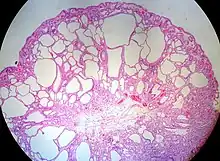

| Hyperplastic polyp of the stomach | Stomach | Elongated, tortuous, and cystic foveolae separated by edematous and inflamed stroma.[4] | ![]() |

Gastric hyperplastic polyposis | |